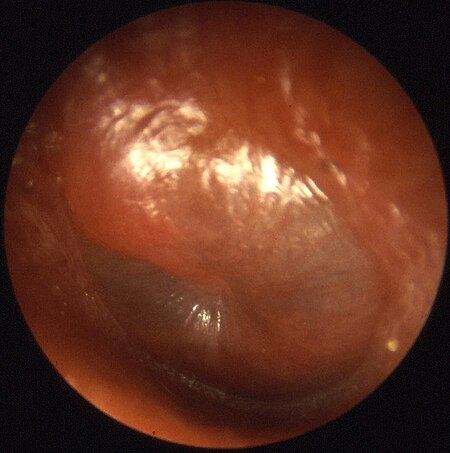

شکل پرده گوش متورم که به طور معمول در اوتیت میانی حاد (acute otitis media) دیده میشود.